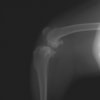

術後左後肢側面像

術後左後肢正面像

手術前後のTPA(脛骨高平部の角度)を測定しています。

約29°から約10°へ矯正されています。

術前のTPAは左後肢33.1°右後肢26.8°でしたがTPLO実施により左後肢5.5°右後肢12°に矯正されました。